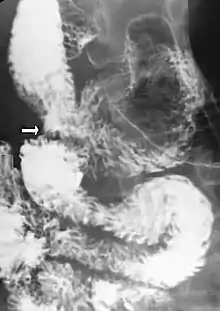

Upper gastrointestinal series showing extreme duodenal dilation (white arrow) abruptly preceding constriction by the SMA.- Ultrasound showing SMA syndrome[19]